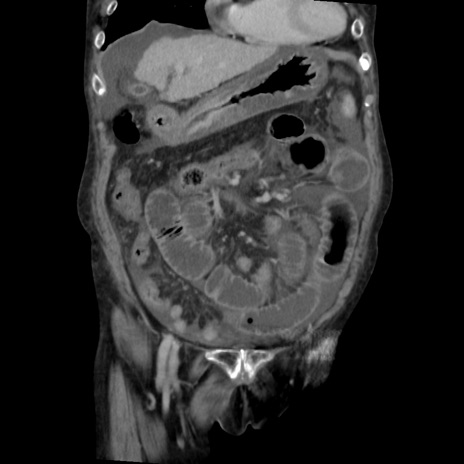

症例31(冠状断像)

矢状断像